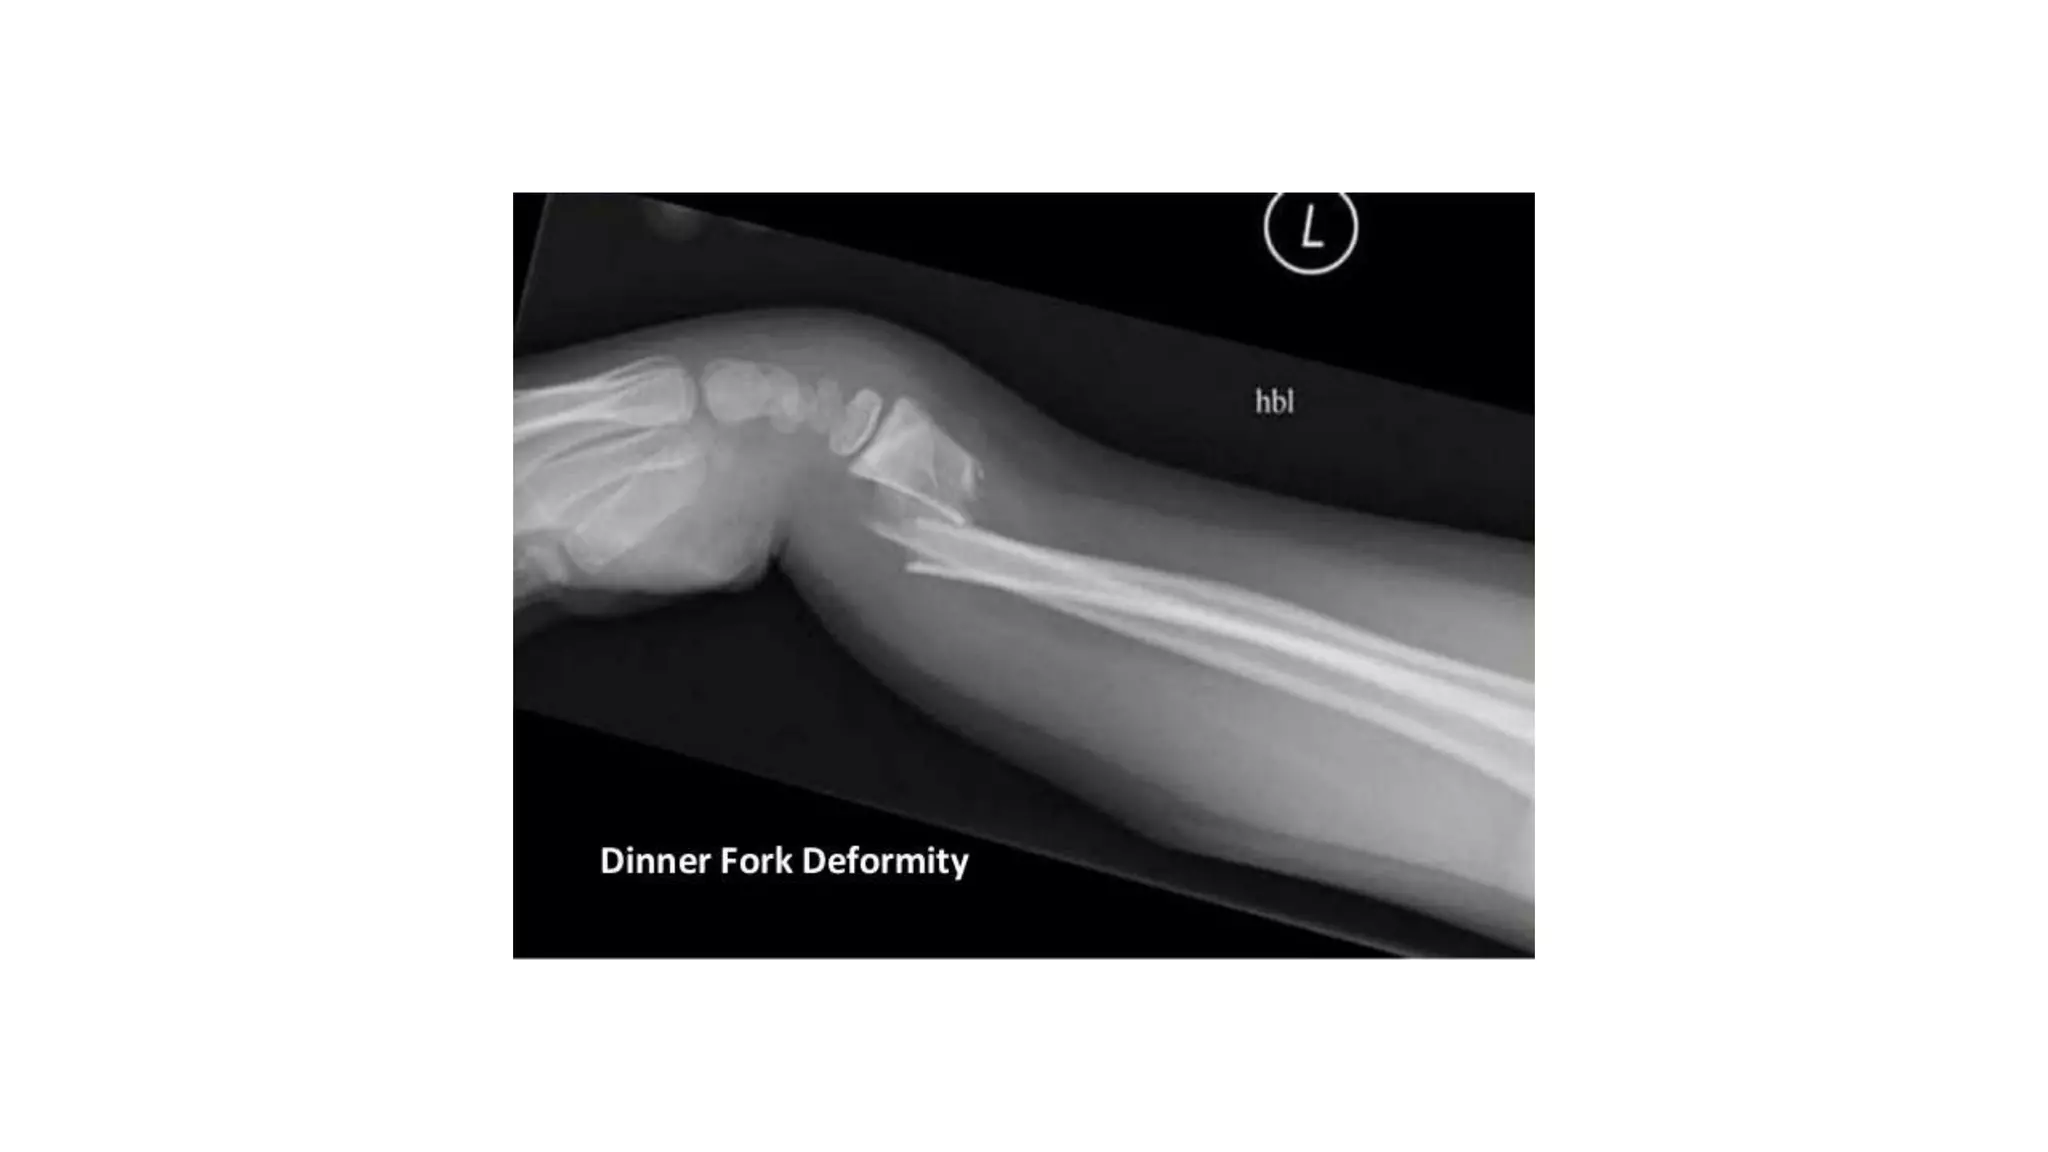

- ‘Dinner fork’ deformity:

with prominence on the back of the wrist &

a depression in front.